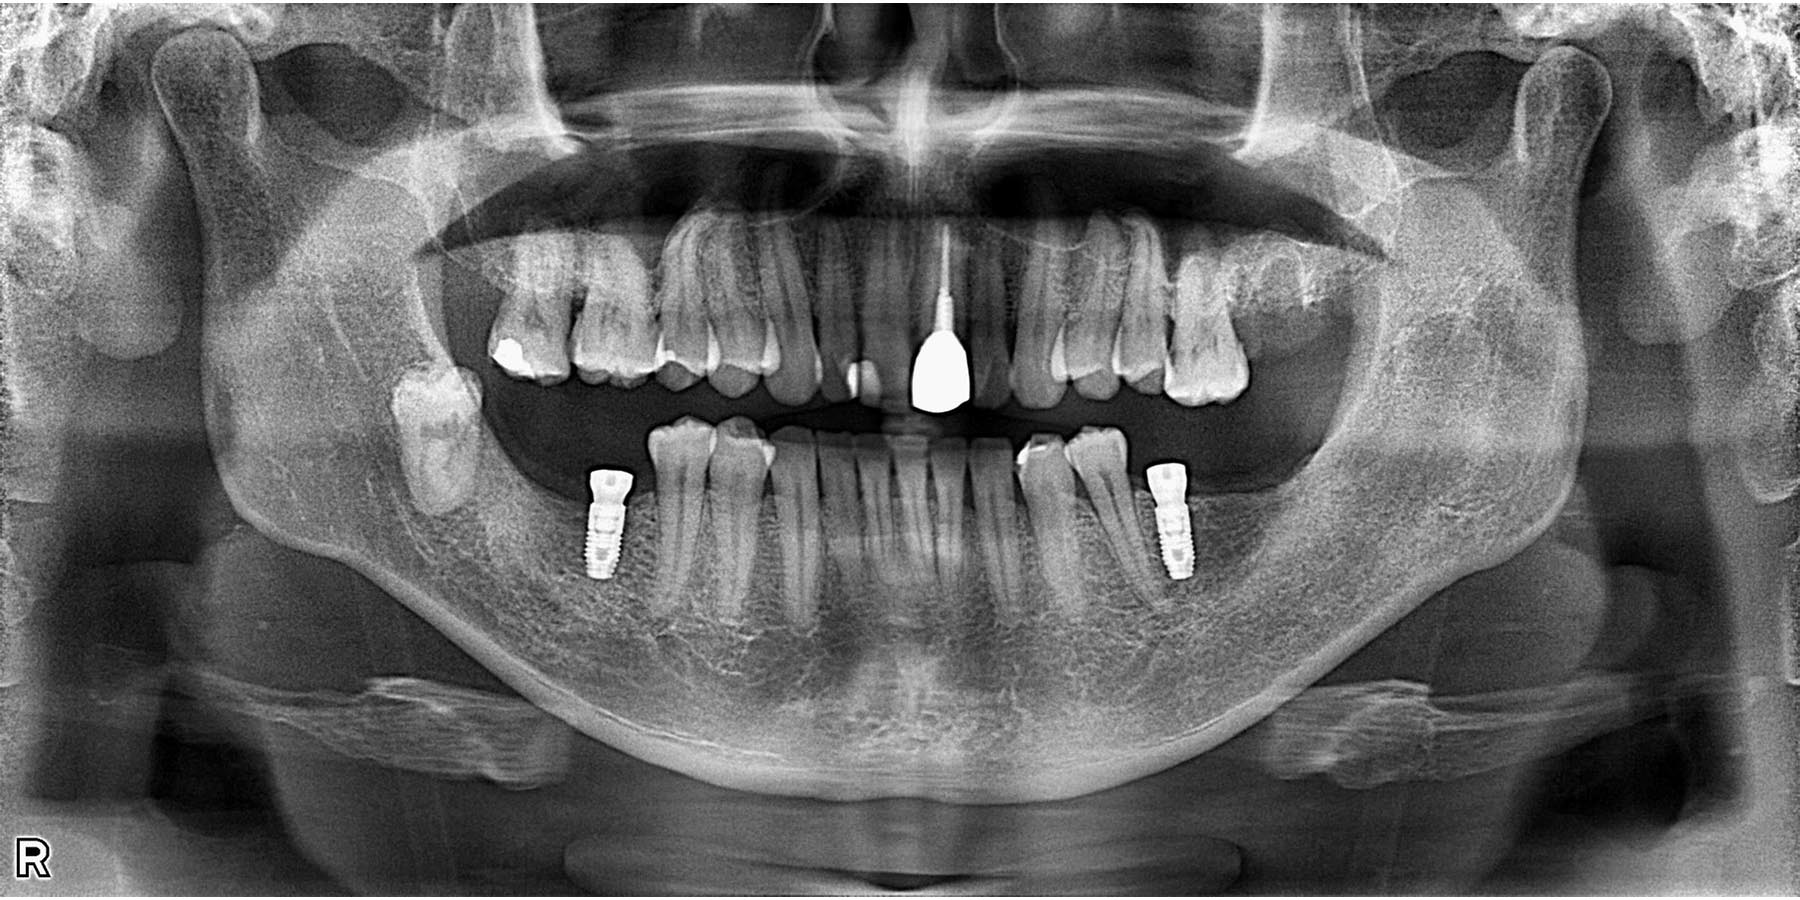

治療後

インプラント埋入後

被せ物セット完了